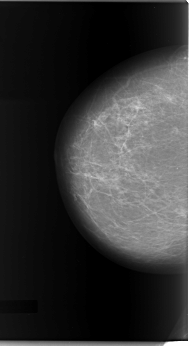

C_0081_1.LEFT_MLO

LEFT_CC LINES 6032 PIXELS_PER_LINE 3544 BITS_PER_PIXEL 12 RESOLUTION 50 OVERLAY

FILE: C_0081_1.LEFT_CC.OVERLAY

TOTAL_ABNORMALITIES 1

ABNORMALITY 1

LESION_TYPE MASS SHAPE IRREGULAR MARGINS SPICULATED

ASSESSMENT 5

SUBTLETY 4

PATHOLOGY MALIGNANT

TOTAL_OUTLINES 1

BOUNDARY